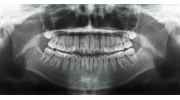

| 治療前後の比較